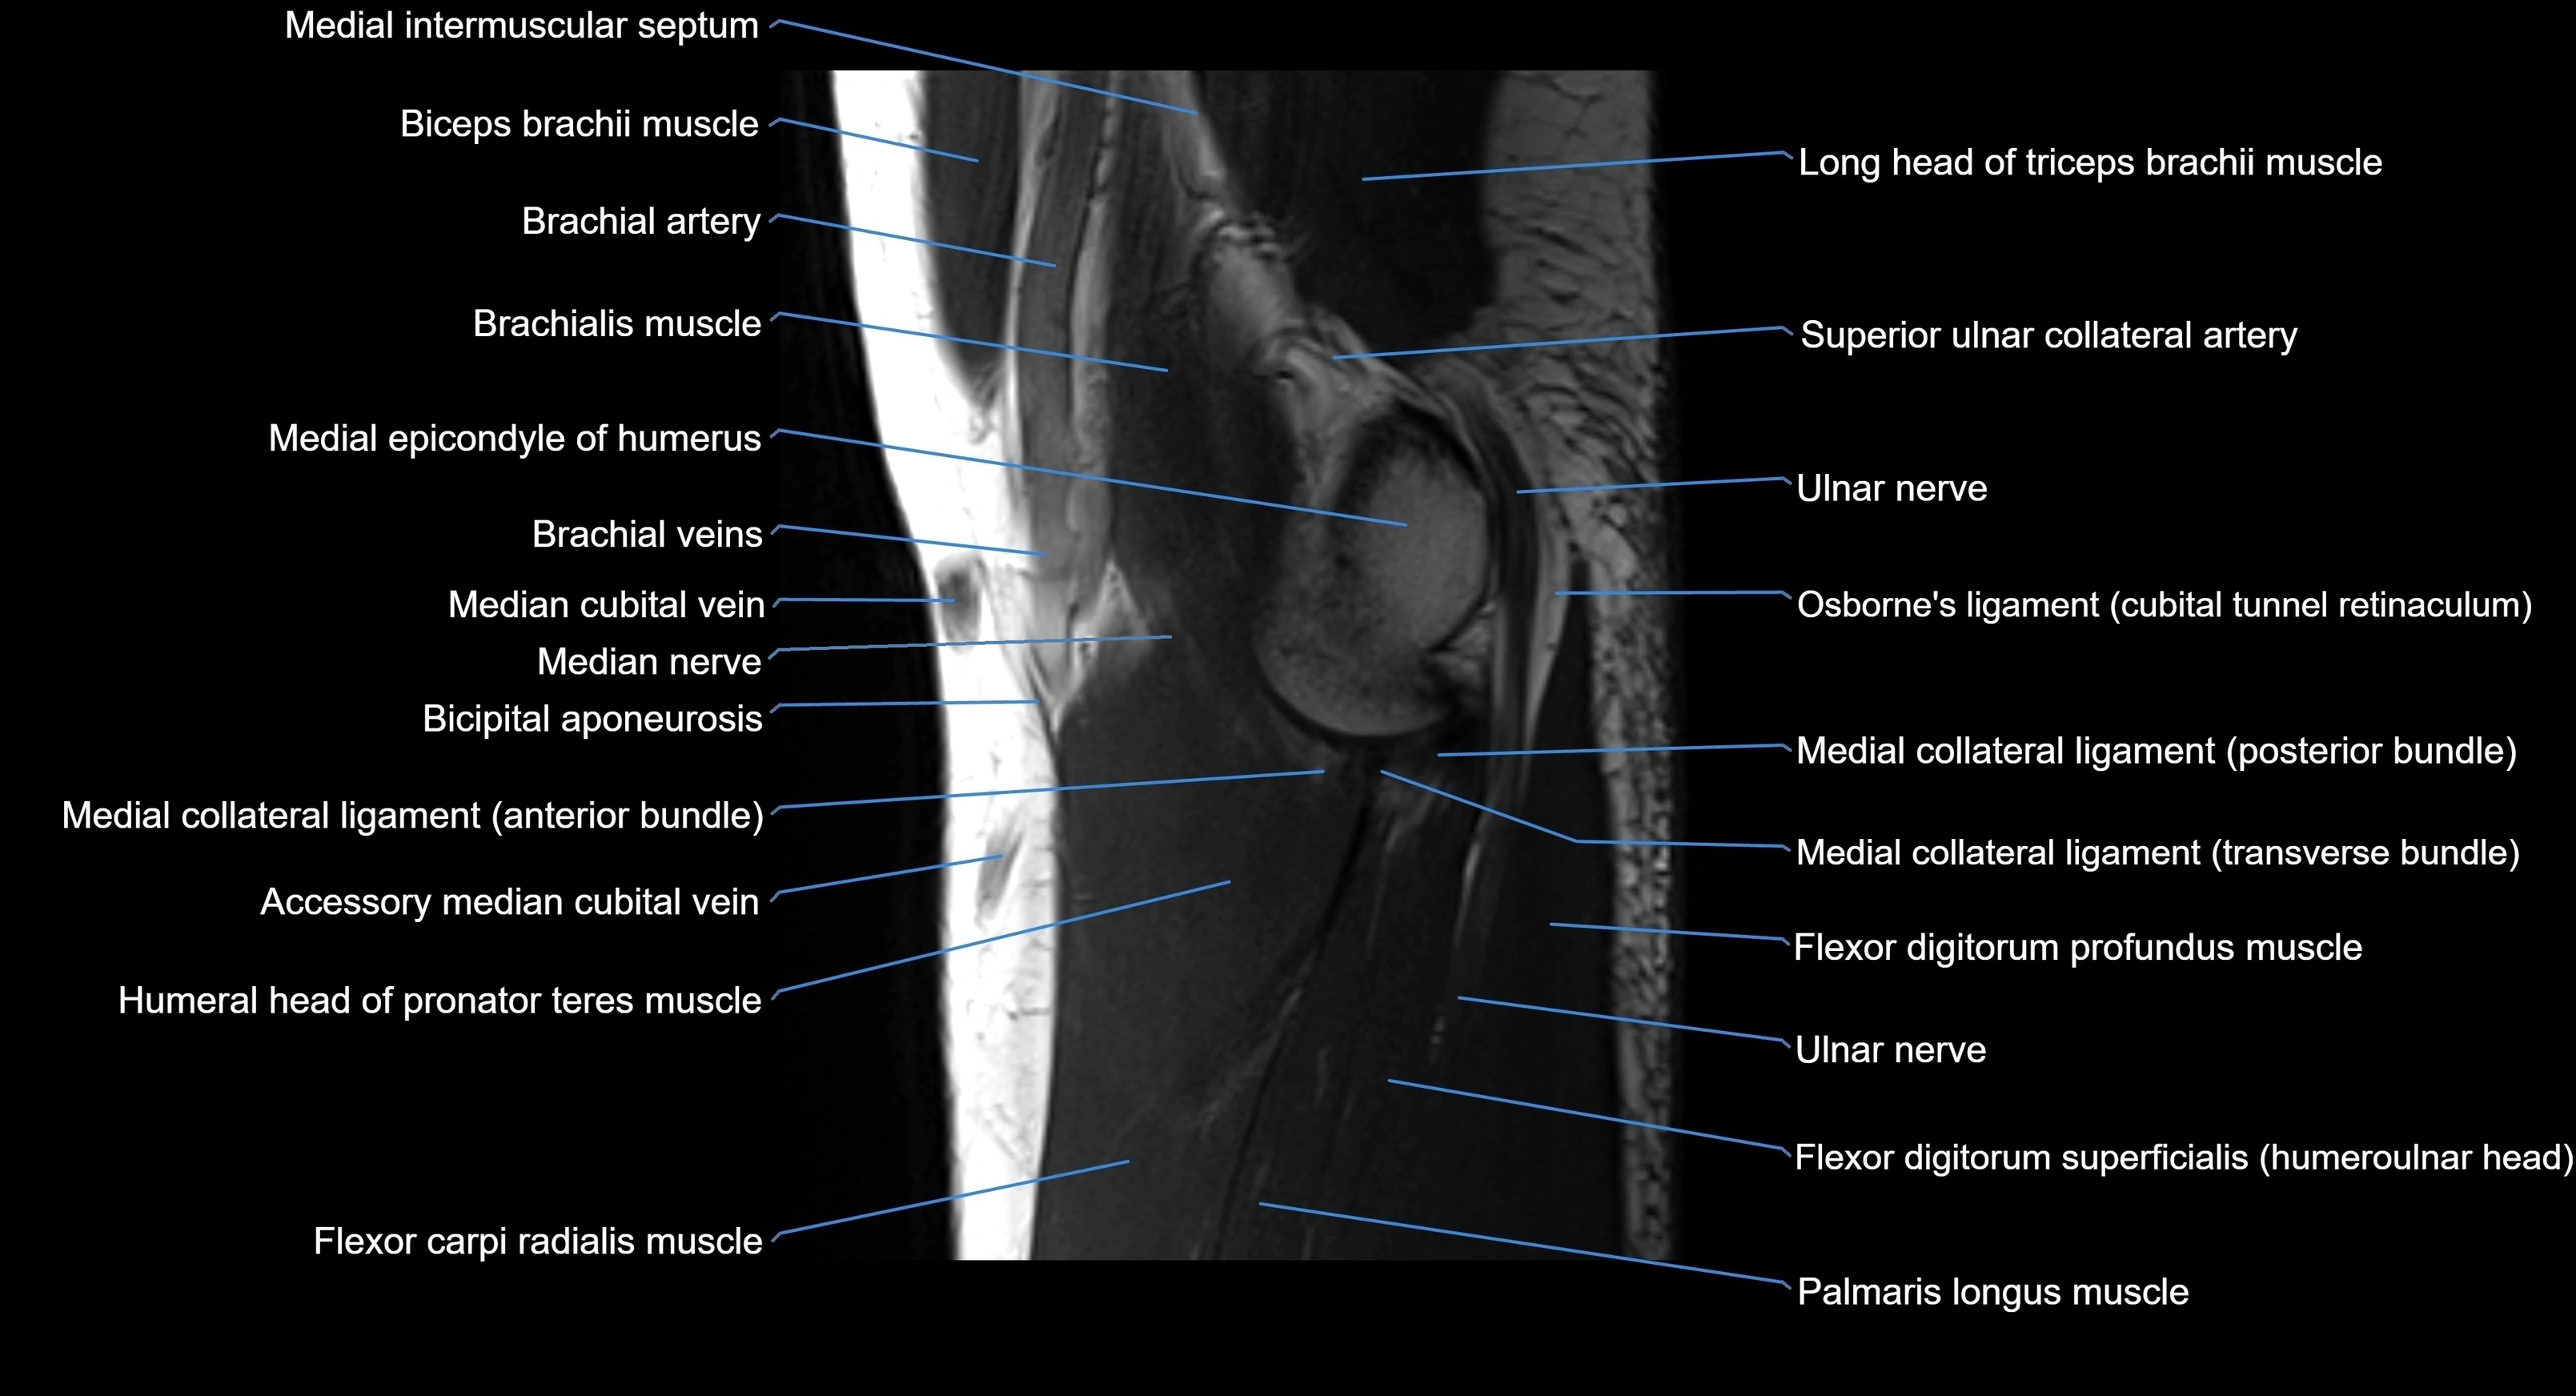

MRI image

image